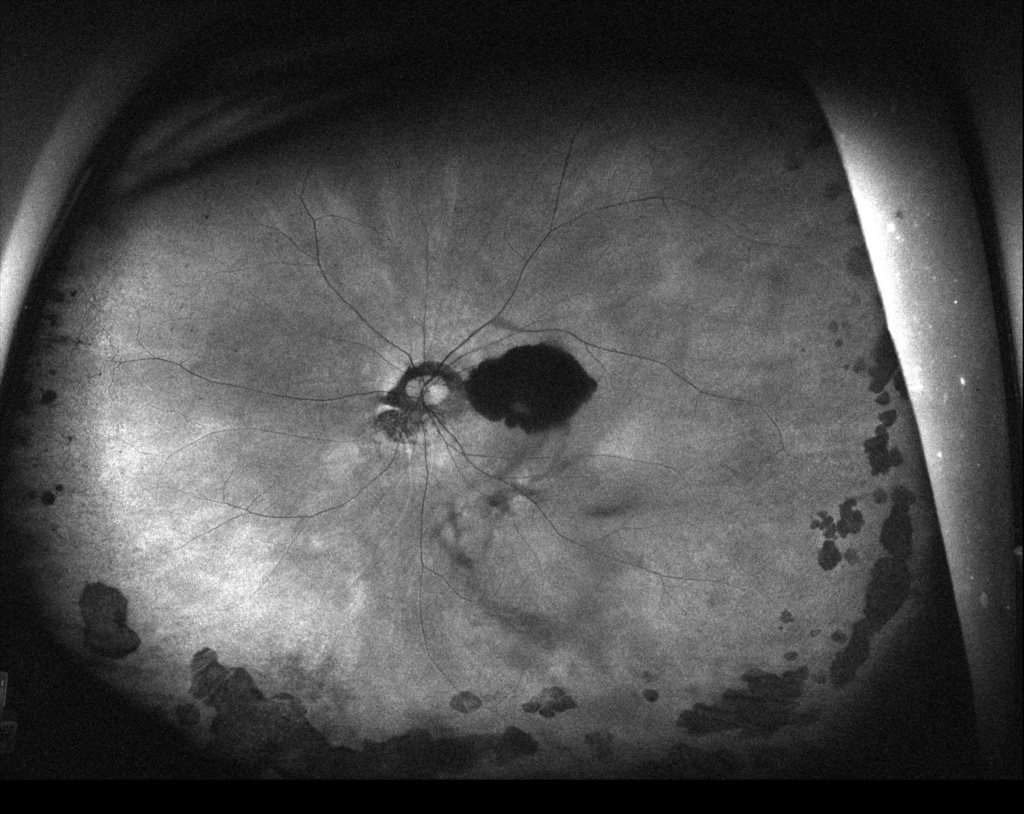

初診時

網膜下出血と出血性PEDがみられる。

低いPEDの内部は中等度~低反射が混在しており新生血管と考えられる。